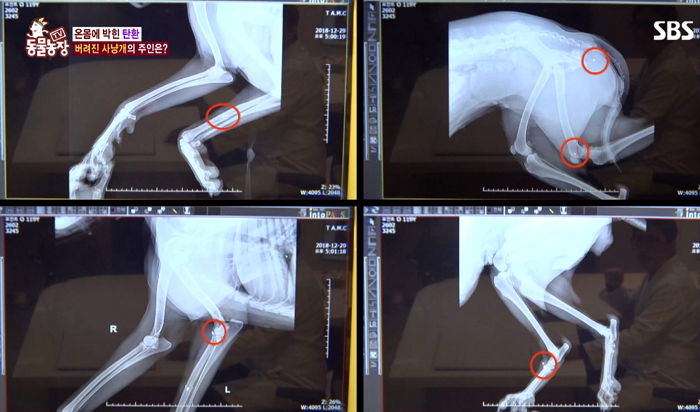

검사 결과, 사냥개의 몸에서는 직경 4mm 정도의 탄환이 발견됐다. 심지어 한 군데가 아닌 몸 5곳 이상에 탄환이 박혀져 있어 충격을 안겼다.

파편이 으스러진 정도를 통해 당시 충격이 얼마나 컸는지를 짐작할 수 있었다.

수의사는 "탄환만 깨끗하게 제거해서 주변 조직이 괴사 되지 않도록 관리하면 빨리 회복은 될 상황"이라고 말했다.